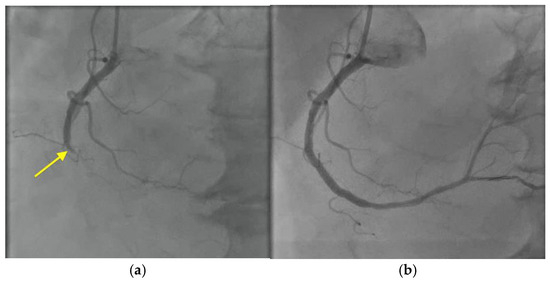

The patient was restarted on piperacillin-tazobactam and was prepared for an urgent TV replacement. Intraoperatively, there was a 3 cm vegetation on the anterior leaflet of the TV, with >50% of the leaflet destroyed (Figure 7). He had a successful TV replacement with a bioprosthetic valve with a residual paravalvular leak (Figure 8, Videos S10 and S11). His blood and valve cultures were negative. However, 16S ribosomal RNA amplicon sequencing (University of Washington, Seattle, WA, USA) performed on the resected valve tissue was consistent with C. canimorsus infection. Antibiotic treatment was continued with piperacillin-tazobactam.

Figure 8. Postoperative transthoracic echocardiogram showing: (a) new bioprosthetic tricuspid valve (red circle) and (b) residual paravalvular leak (red arrow).